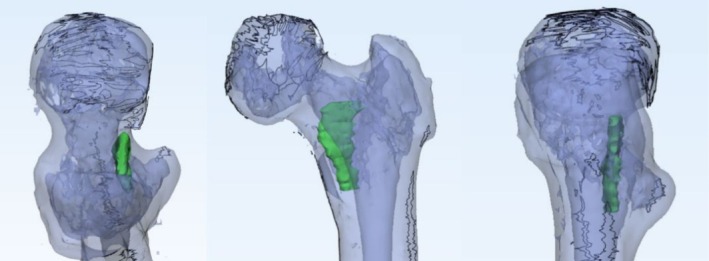

Methods: A retrospective analysis was conducted on 350 femoral neck fracture patients (aged 18-65 years) treated with closed reduction and three cannulated screws fixation at a single institution from 2015 to 2020. Evaluate the clinical and imaging information of patients such as sex, age, body mass index, Garden classification, calcar femorale injury situation, computed tomography Hounsfield units (CT HUs), comorbidities (e.g., diabetes, hypertension etc.) and complications (femoral neck shortening, nonunion, and femoral head necrosis). CT-based 3D reconstruction was used to analyze calcar femorale morphology. Statistical analyses included univariate and multivariate logistic regression to identify independent risk factors.